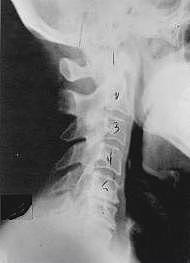

Subluxation Degeneration - Phase One Phase One Subluxation Degeneration is seen in subluxations that have been present for up to twenty years. This phase is characterized with a loss or change in the normal curve in the spine. On this example you can see that the normal forward (lordotic) curve is lost. This spine even has developed a reverse curve in the neck. The disc spaces have also begun to exhibit a slight change in shape. One good point is that the bodies of each of the vertebrae (the square part in front) still exhibits clean clear borders. Segmental motion may be abnormal but overall motion is probably not affected. Chiropractic reconstructive care for a phase one can take from 6 to 18 months. More than 80% of people with Phase One Subluxation Degeneration have no pain. Therefore, if left uncorrected, phase one continues to progress with time until it eventually reaches the next phase.